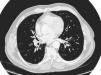

La tomografía computarizada objetivaba la presencia de un nódulo cavitado de 3,8cm de diámetro, de densidad heterogénea, en el lóbulo inferior derecho, el cual entraba en contacto con la pleura, además de adenopatías paratraqueales derechas en el límite alto de la normalidad (fig. 1). La fibrobroncoscopia resultó ser negativa para malignidad, mientras que la punción aspirativa con aguja fina (PAAF) confirmó la presencia de células metastásicas de adenocarcinoma de colon. La tomografía por emisión de positrones mostraba un área con actividad metabólica elevada e irregular, de unos 3cm de diámetro, localizada en la periferia de la región basal del campo pulmonar derecho, así como una actividad difusamente aumentada en las regiones hiliares, indicativa de focos inflamatorios mal definidos. El resto de la captación de fluoro-2-desoxiglucosa en otras zonas carecía de significación patológica, a excepción de un pequeño foco situado en la región prostática.